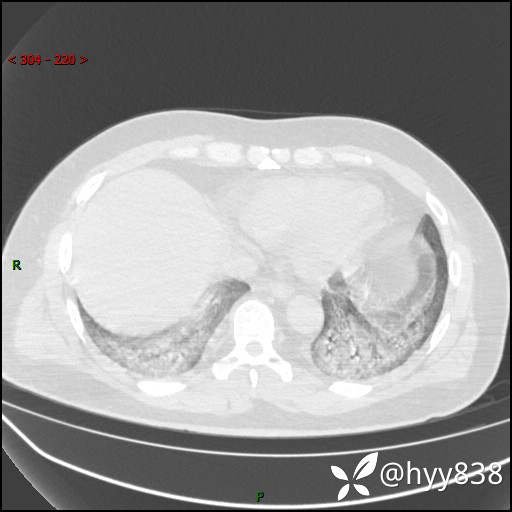

第一次胸部CT

第二次CT(7天后)